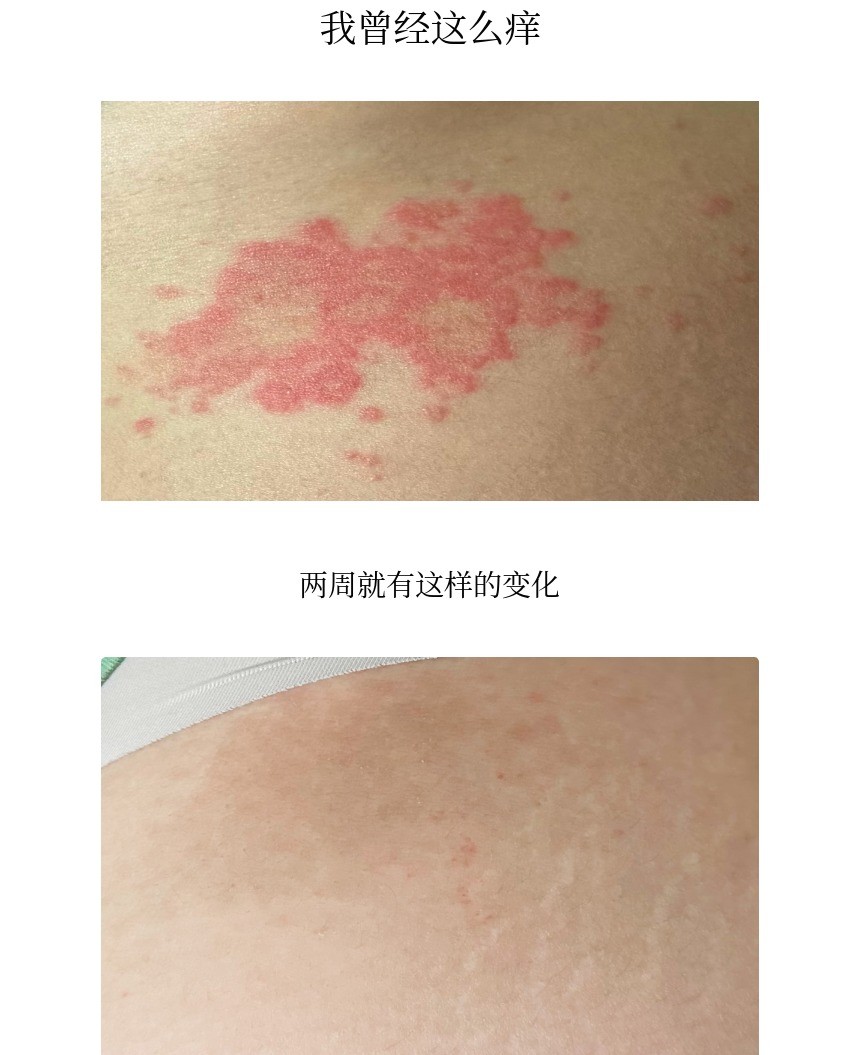

这是之前版本的用户照片评价。

我曾经是连化妆和穿牛仔裤都做不到的人。

体验过瘙痒的人一定会明白原因。

化妆的那天皮肤就会变糟,

穿牛仔裤的那天会更痒,而且材质厚,即使痒也无法隔着衣服抓挠。

但现在我真的好多了。

这不仅仅是我一个人的故事,能向大家介绍这款面霜,我感到非常感激。

也希望你们像我一样,

真心希望你们不再有忍无可忍只能起身用冷水冲澡的夜晚。